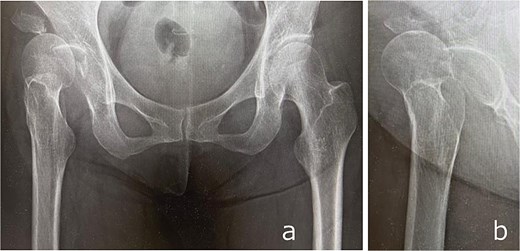

Plain radiographs demonstrated an anterior dislocation of the right hip with associated acetabular fractures (Fig. 1). Computed tomography (CT) after closed reduction revealed fractures of the anterior inferior iliac spine (AIIS), the anterior acetabular wall, and an intra-articular femoral head fracture fragment (Fig. 2). The injury was classified as Pipkin type IV [2] and Brumback type 4B [3].

Anteroposterior (a) and lateral (b) radiographs of the right hip obtained at initial presentation, demonstrating anterior hip dislocation associated with acetabular and anterior inferior iliac spine fractures.